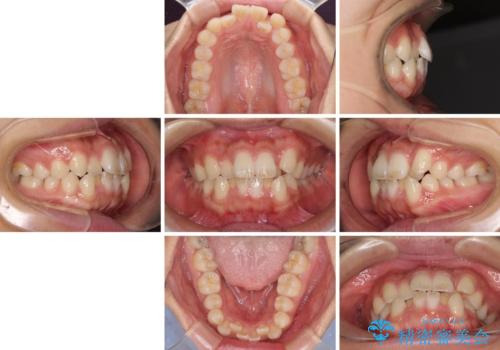

- 前歯のデコボコと口元の突出感を気にして来院された患者様です。

上下左右第一小臼歯4本を抜歯し、ワイヤー装置にて口元を引っ込めるよう矯正治療を行うこととしました。

非常にスムーズに歯列移動が行われ、当初は2-2.5年を予想していましたが、僅か1年4ヶ月で治療を終えることができました。